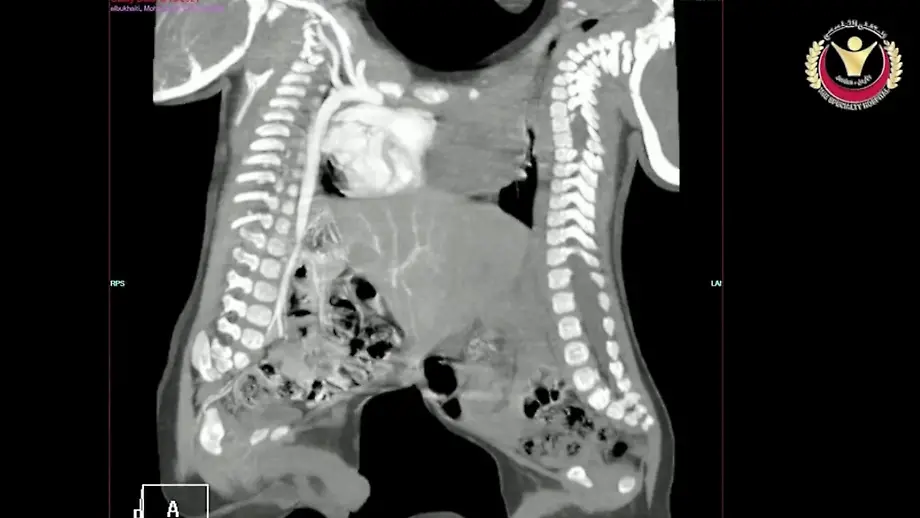

04.10.2021, 08:37 UhrAhmed und Mohammed kommen als siamesische Zwillinge im Bürgerkriegsland Jemen zur Welt. Da die medizinische Versorgung vor Ort schlecht ist, wird das Zwillingspaar nach Jordanien geflogen. Dort trennt man sie in einer Premieren-OP, doch die Ärzte halten den Eingriff zunächst unter Verschluss.